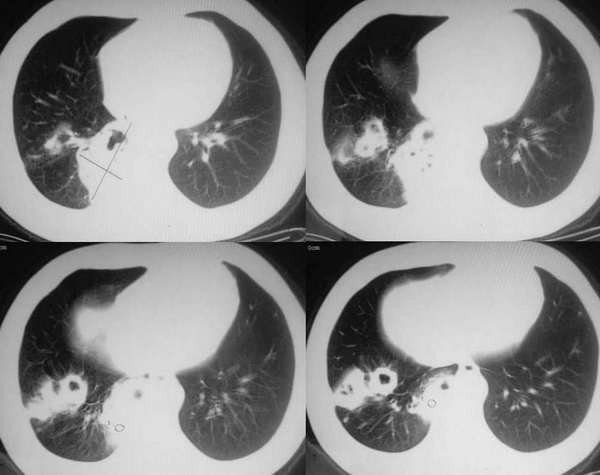

右肺下叶基底段团状阴影,其内见多发不规则空洞,无液平;两肺多发大小不等结节影,纵隔淋巴结肿大,考虑:肺癌伴肺内及纵隔淋巴结转移

右肺下叶基底段及两肺多发大小不等结节影,其内见多发不规则空洞,无液平;纵隔淋巴结稍肿大,考虑:霉菌感染

右肺下叶基底段团块状病灶,其内见偏心性空洞,洞内未见液平面,可见壁结节;双肺野及双侧胸膜见多发大小不等软组织密度结节影,边缘较光滑,部分肺内结节有空洞形成;纵隔内见有重大淋巴结;右侧见少量胸腔积液。

结合临床考虑:1、右肺癌并双肺、胸膜转移,考虑鳞癌可能性大。2、纵隔淋巴转移。3、建议查痰找癌细胞。

影像表现:两肺大小不等结节,有融合、有空洞,洞壁薄厚不均,

两肺外周胸膜下可见多发大小不等的结节影,边缘稍模糊,可见细长毛刺,右肺下叶病灶部分融合成片状,内出现多房空洞,部分内有小液平面,内壁较光整,壁厚不规则。考虑真菌感染(隐球菌)。

ct所见;两肺胸膜下多发散在大小不一结节状影,部位以右侧为主,多在胸膜下,多数结节内可见不规则空洞,壁厚薄不均,未见液平。